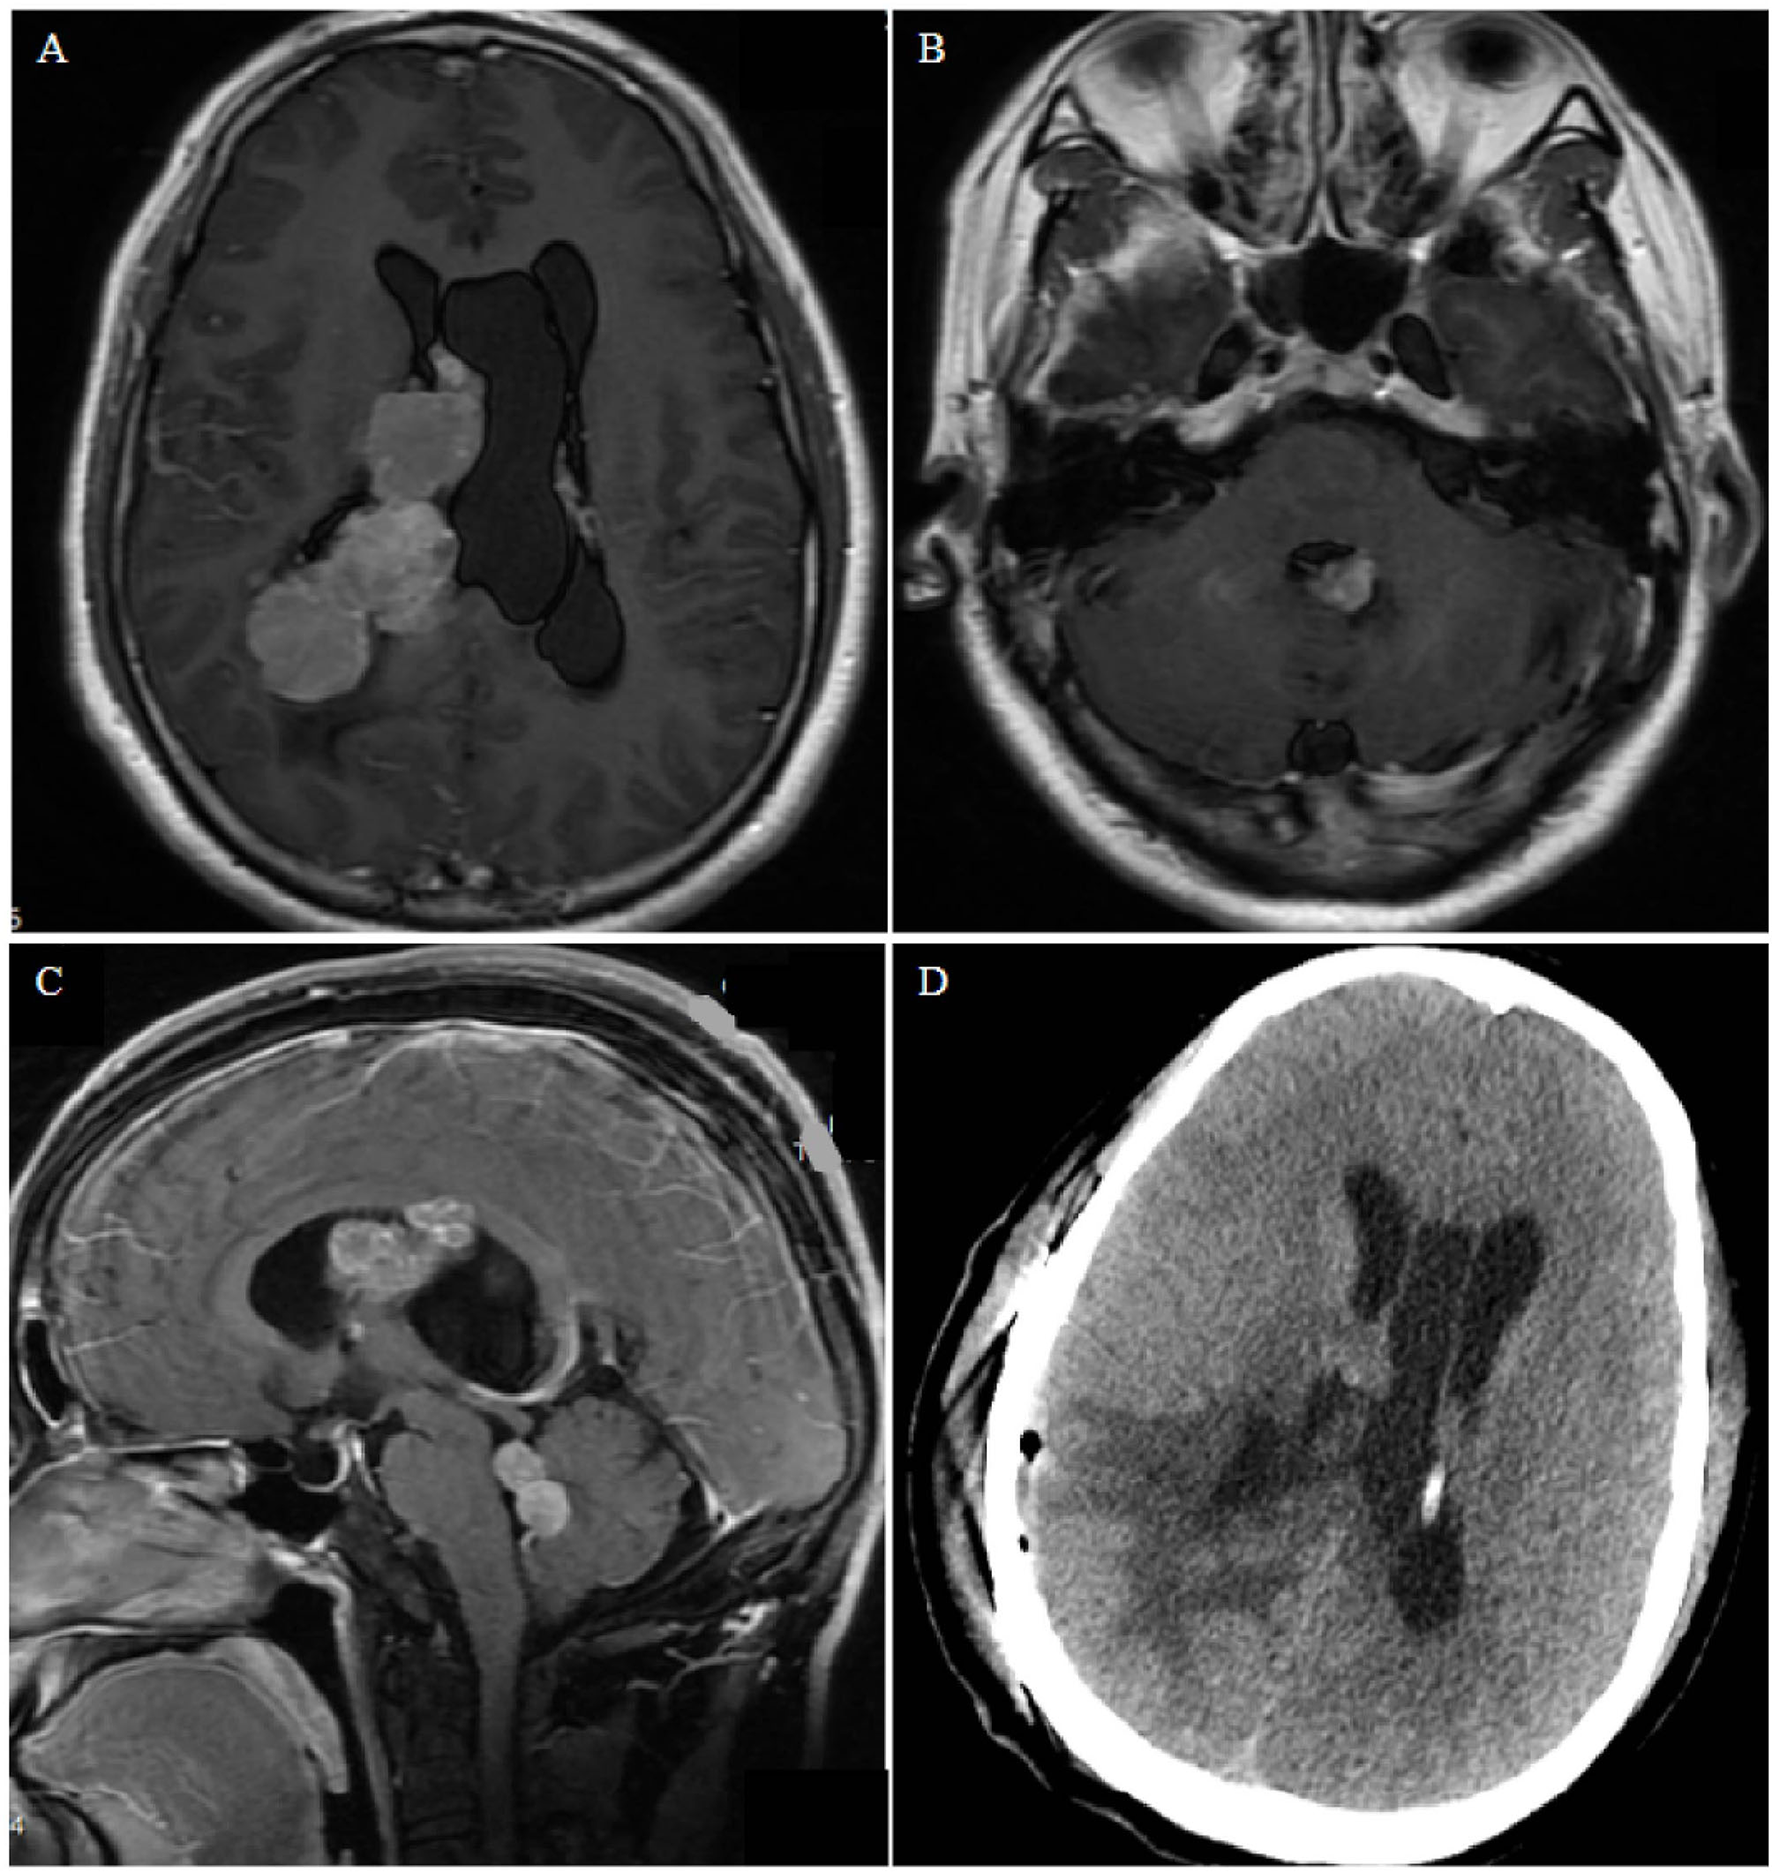

Case 2. (A,B) Contrast-enhanced T1-weighted axial images show nodular bead-like lesions in the right and fourth ventricles. (C) Sagittal magnetic resonance images showing multiple lesions occupying the midbrain aqueduct and fourth ventricle. (D) Postoperative computed tomography shows edema of brain tissue and no bleeding in the operative cavity.

A 35-year-old man presented with dizziness, nausea, and vomiting for 2 months. No obvious abnormalities were noted on physical examination, and no past underlying diseases were identified. Magnetic resonance imaging (MRI) examination revealed multiple lesions in the right lateral ventricle, middle cerebral aqueduct, and fourth ventricle, some of which were cluster-like, accompanied by hydrocephalus, with avid enhancement (Figure 3). Preoperative diagnosis could not be performed, considering the possibility of metastases. Most of the intraventricular tumors were resected via the temporo-occipital approach. During the operation, the lesions were observed to originate from the choroid plexus. Microsurgical resection was uneventful, and postoperative pathology revealed diffuse large BCL, with no significant postoperative complications. The patient refused further radiotherapy and chemotherapy and died 2 months later.